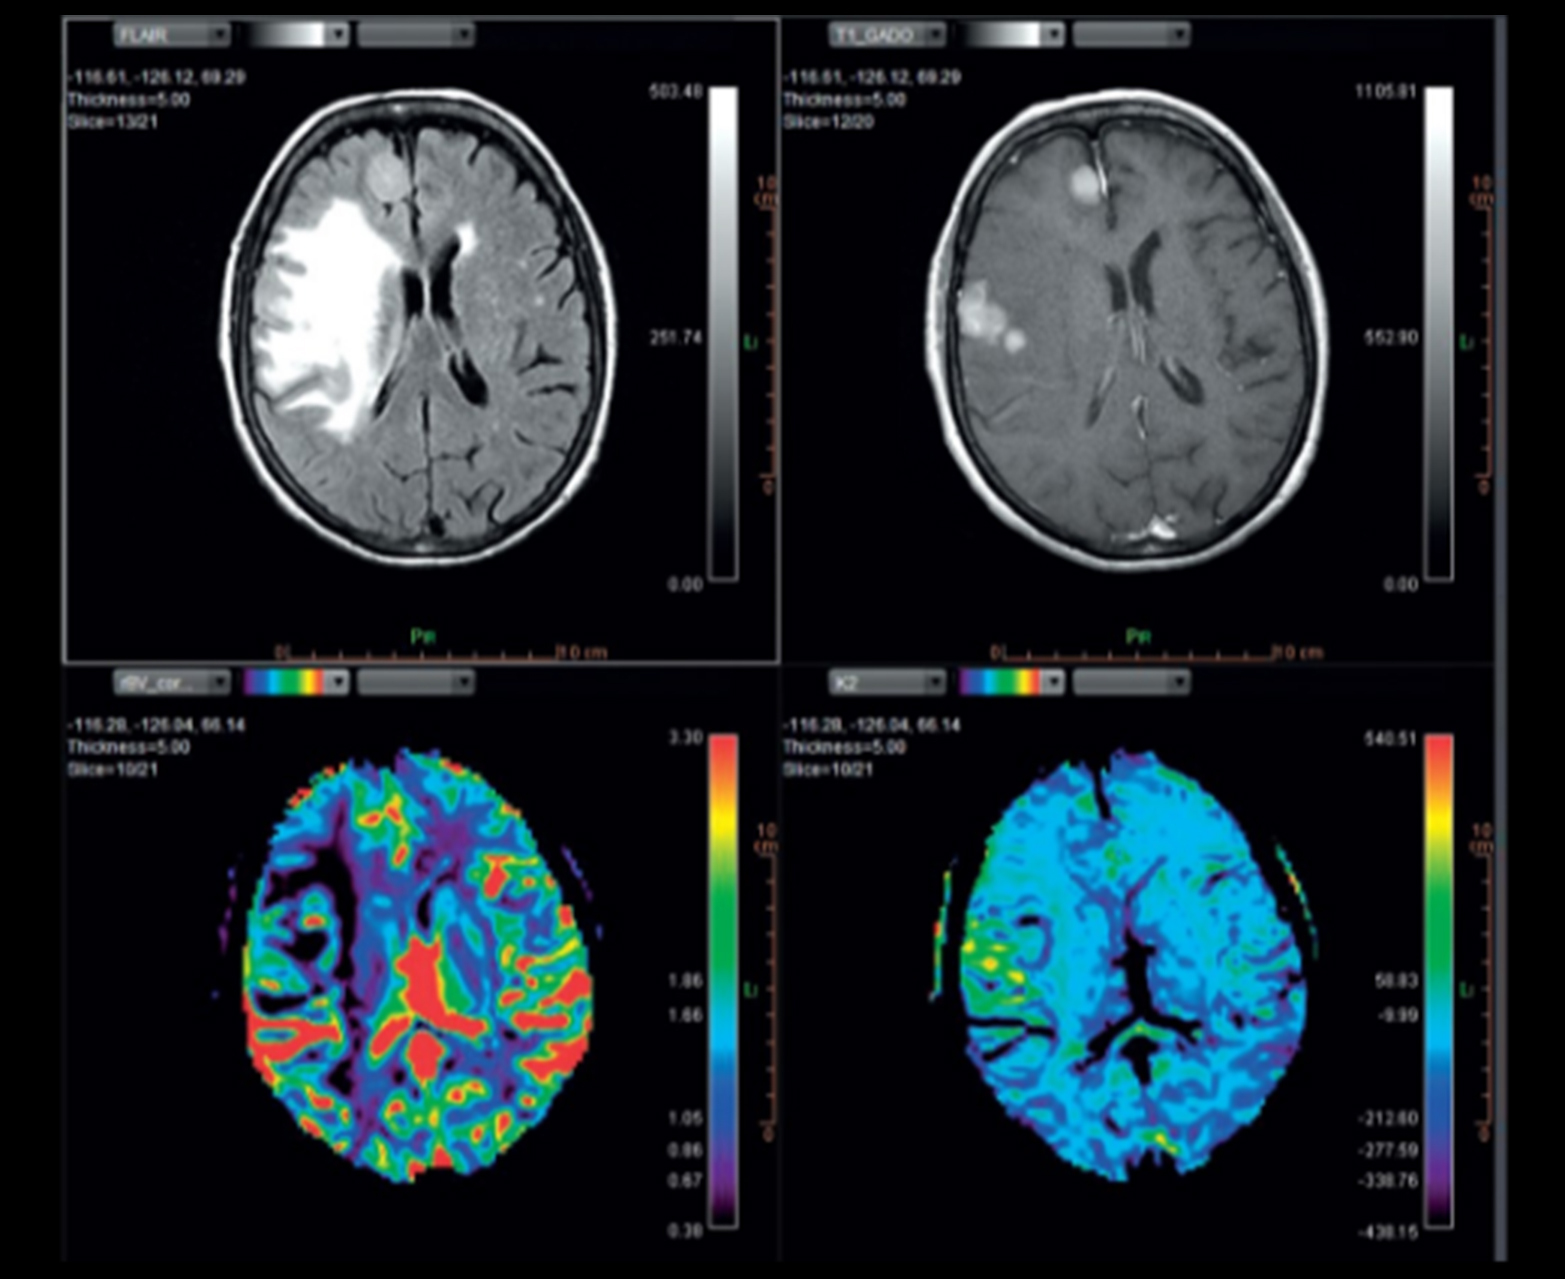

Многопараметрическое настраиваемое отображение карт диффузии и перфузии, включая карты rCBV_corrected и K2

Отслеживание волокна и объединение с обычными картами